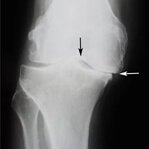

Choroba zwyrodnieniowa stawów stopniowo niszczy tkankę chrzęstną i prowadzi do deformacji stawów. Z czasem nawet najprostsze ruchy stają się niemożliwe, a ból staje się stały. Odpowiednia terapia pomaga zatrzymać postęp choroby.

Obrzęk i stan zapalny stawu kolanowego są sygnałem ostrzegawczym poważnych zaburzeń. Bez leczenia może to prowadzić do całkowitej utraty sprawności ruchowej i konieczności interwencji chirurgicznej. Reaguj natychmiast na pierwsze objawy!